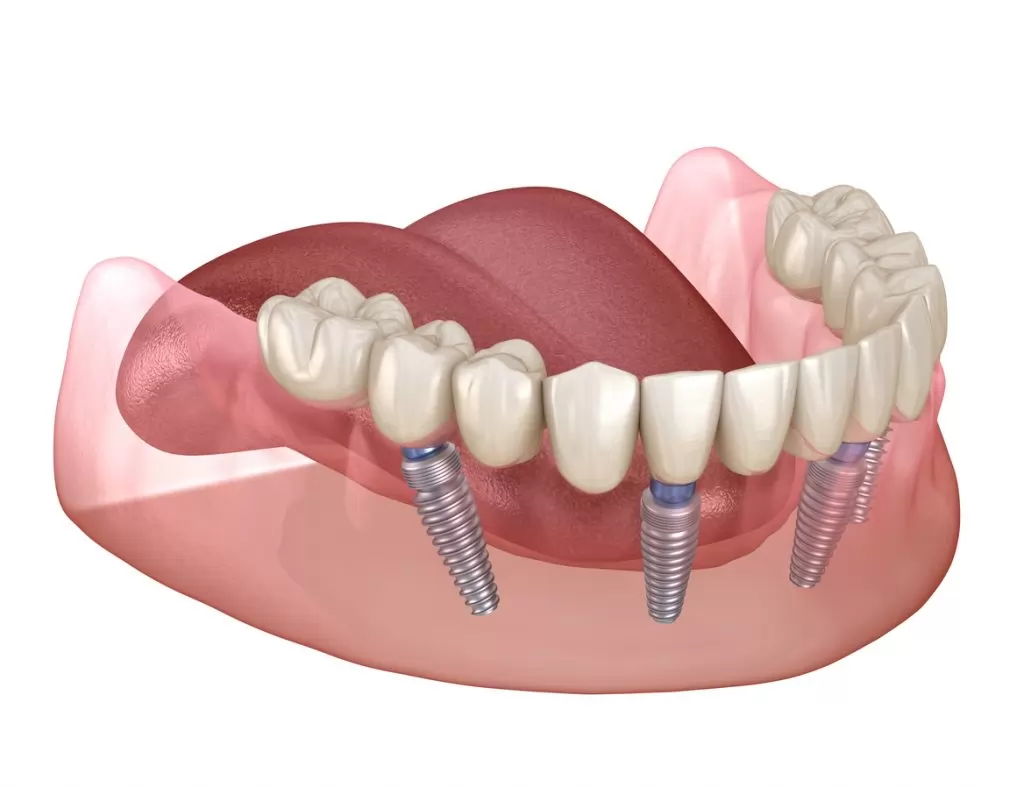

All-on-4 implant tedavisi, tüm dişlerinizi tek seans içerisinde çıkartılıp yerine 4 adet implant üzerine sabitlenen bir köprü ile değiştirmektir. Bu tedavi yöntemi, diş eksiklikleri olan kişilere daha hızlı ve daha kolay bir diş restorasyonu sağlar.

All-on-4 implant tedavisi, bir cerrahi işlemle yapılır. Tedavi sırasında, öncelikle diş etleri kaldırılır ve dişler çekilir. Sonrasında, implantlar çene kemiğine yerleştirilir ve geçici bir köprü takılır. Yerleştirilen implantlar iyileşme sürecinde kemikle kaynaşır ve kalıcı köprü yerleştirilir.